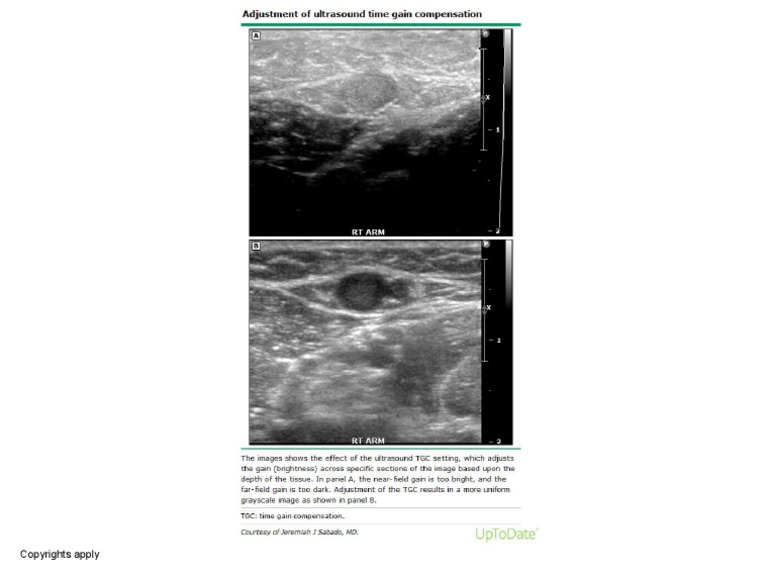

Adjustment of Ultrasound Time Gain Compensation PDF Ultrasound Gain Adjustment Proper imaging requires the examiner to adjust the signal gain, which exists for each of the three us. Gain, tgc and output power. This compensates for the attenuation that occurs with increasing depth. Gain and tgc are controls that are frequently adjusted several times during an exam. If you have considered all of these suggestions and your image is still. Ultrasound Gain Adjustment.